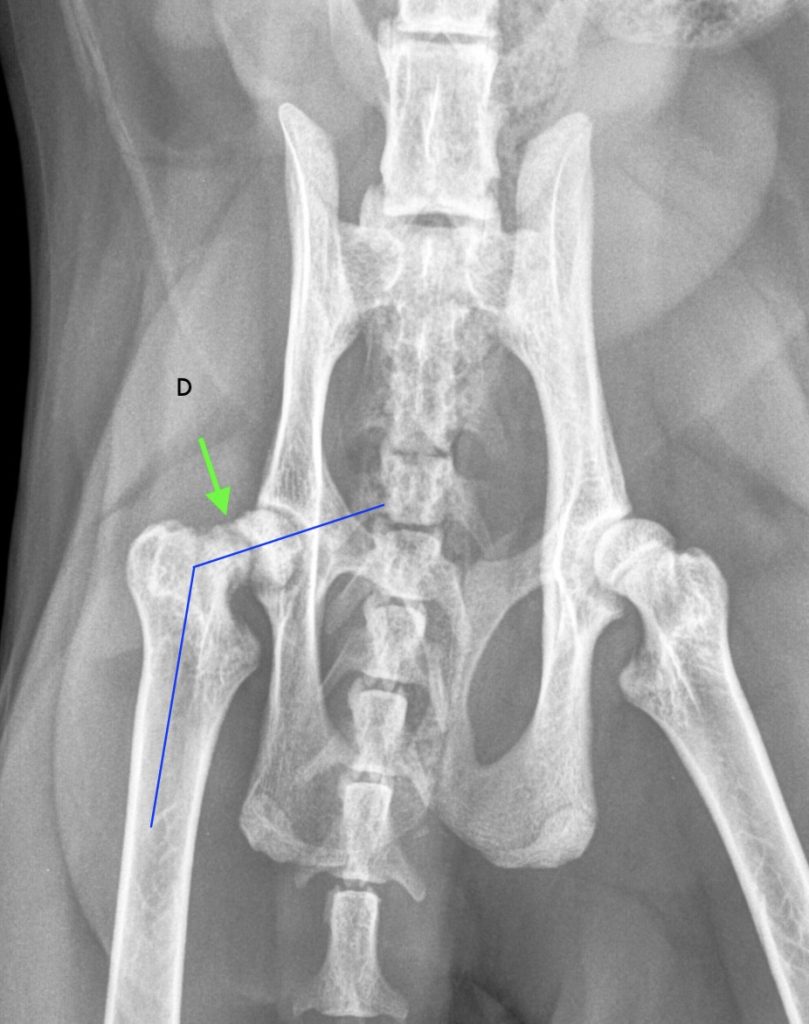

Après une prise en charge de la douleur des radiographies du bassin et des postérieurs sont réalisées (photo 1a et 1b).

Les radiographies du bassin montrent une fracture oblique complète, peu déplacée, aux contours mal délimités du cartilage de croissance de la tête fémorale droite avec un discret déplacement latéral et une angulation accrue du col fémoral. La trame osseuse métaphysaire et épiphysaire adjacente au trait de fracture est d’opacité augmentée.

En conclusion, on observe une fracture du cartilage de croissance de la tête fémorale droite de type Salter Harris I associée à une sclérose adjacente au trait de fracture.

Les images radiographiques, les commémoratifs et l’anamnèse sont pathognomoniques d’un glissement épiphysaire de la tête fémorale (« slipped capital femoral epiphysis »). Une disjonction épiphysaire traumatique ou une infiltration tumorale osseuse (ostéosarcome) sont beaucoup moins probables.

Il est parfois nécessaire de réaliser des projections ventrodorsales en flexion et en extension, grâce à une analgésie efficace, pour mieux visualiser la fracture.